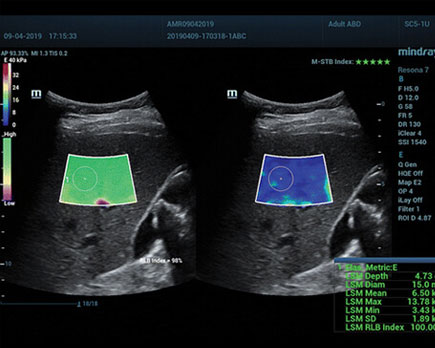

الاستوگرافی چیست؟ کاربرد، مزایا و هزینه سونوگرافی الاستوگرافی